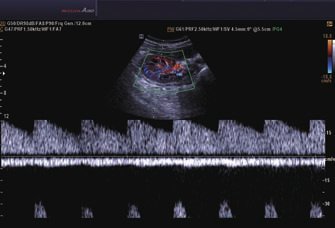

• Farb-Doppler

• Pulsed Wave (PW)-Spektral-Doppler

• Continuous Wave (CW)-Doppler

• Color Opt Flow™ bietet kraftvollere Farben und verbessert die Bildqualität.